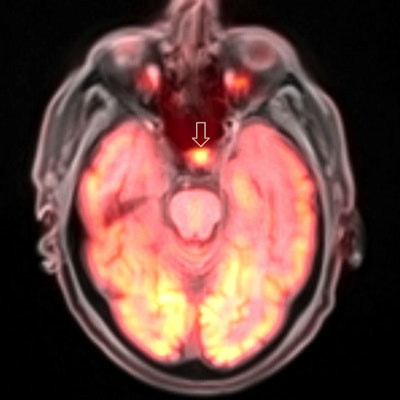

PET/MRI

For all its promise, PET/MRI has never been chosen by the Minnies judges as the Hottest Clinical Procedure in radiology.

Perhaps that's because, for all of the "wow" factor entailed by the fusion of metabolic PET images with anatomical MRI scans, the scanners still remain astronomically expensive, far beyond the means of all but the most advanced academic hospital.

One can't help but be impressed by the quality of the images -- but are they clinically useful? One study questioned whether the PET/MRI was really necessary for at least one application: cardiac sarcoidosis. Another found that PET/MRI with a gallium-68 prostate-specific membrane antigen-11 (PSMA-11) radiopharmaceutical was equivalent to other tools for assessing the progression of prostate cancer -- making one wonder why it's worth the extra expense at all.

Perhaps PET/MRI simply needs a killer use case, the one application for which it and it alone is uniquely suited. PET/MRI may or may not be chosen as the Hottest Clinical Procedure this year, but the fact that it made it to the final round of the Minnies indicates that it's occupying a growing share of radiology's attention.